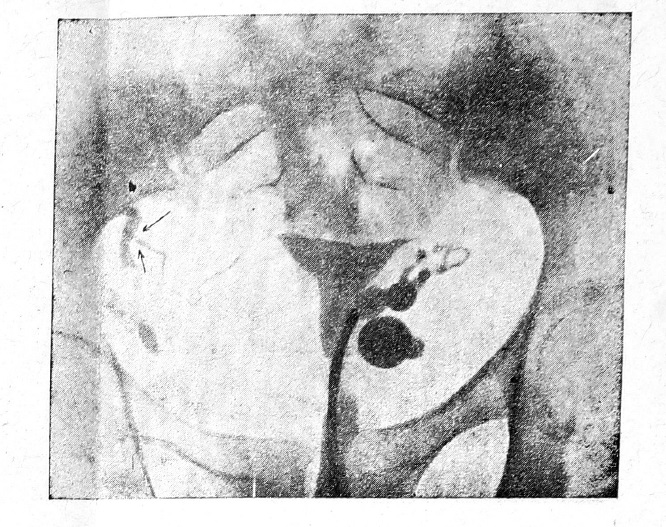

При непроходимости труб последние не заполнялись иодипином и в случаях закупорки их в интрамуральной части они совершенно не контурировались (рис.№ 8). При закупорке труб на протяжении—в pars interstitialis—опредлялся медиальный отрезок, периферический же не контурировался (рис. № 11).

В одном случае с двухсторонней непроходимостью в pars isthmica, где мы сильно подозревали спазм, мы сделали контрольный снимок через несколько месяцев и получили ту же картину. В другом аналогичном случае (рис. № 8) мы сделали повторный снимок через 10 месяцев, причем во избежание предполагаемого возможного спазма начального отдела труб, вызванного давлением контрастного вещества при его введении, мы ввели предварительно лишь 2,5 куб. см. иодипина под весьма слабым давлением и сделали снимок; затем ввели добавоч но 5,0 куб. см. и сделали второй снимок и, наконец, через 20 минут—3-й контрольный, На всех 3-х снимках получилась та же картина-непроходимость труб в pars isthmica, выявленная 10 мес. тому назад.

Рис. 8